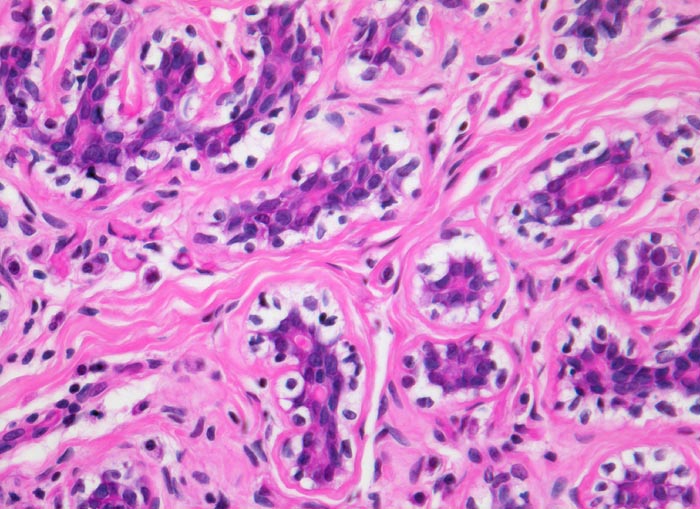

• Biphasischer organoid aufgebauter Tumor bestehend aus kompaktem zellarmem fibroblastärem Stroma, das in konzentrischen Lamellen um verzweigte, miteinander anastomosierende Drüsenschläuche angeordnet ist.

• Die Drüsenschläuche werden durch das Stroma komprimiert.

• Die Drüsen werden ausgekleidet von einer inneren kubischen bis hochprismatischen Zellschicht und einer äusseren abgeflachten Myoepithelschicht mit klarem Zytoplasma.